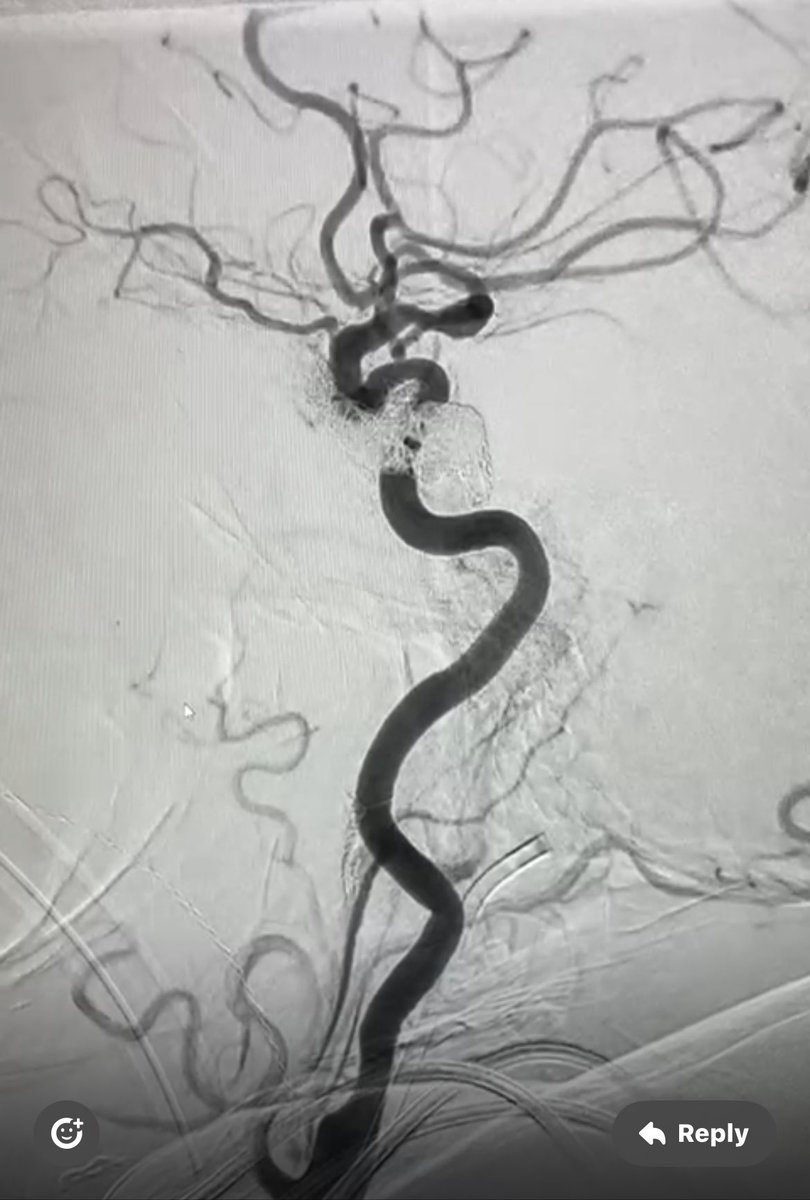

On maximum medical therapy for 2 years Although, Last week developed multiple posterior fossa infarction.(as patient was dependent on diseased RT) Chose LT which was near occlusion of V1/V2 total occlusion of V4, successful stenting using multiple Coronary DES

On maximum medical therapy for 2 years

Although,

Last week developed multiple posterior fossa infarction.(as patient was dependent on diseased RT)

Chose LT which was near occlusion of V1/V2 total occlusion of V4, successful stenting using multiple Coronary DES